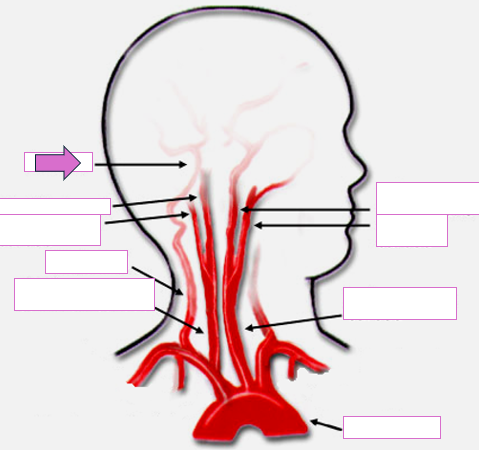

Based on the indicated area, identify this vessel

Brachiocephalic/innominate artery

Right subclavian artery

Right vertebral artery

Right carotid artery

Left carotid artery

Left vertebral artery

Left subclavian artery

True or False: This image shows a Long CCA sonographic appearance

True

Basilar

Right internal carotid

Right external carotid

Vertebral

Right common carotid

Left internal carotid

Left external carotid

Left common carotid

Aortic arch